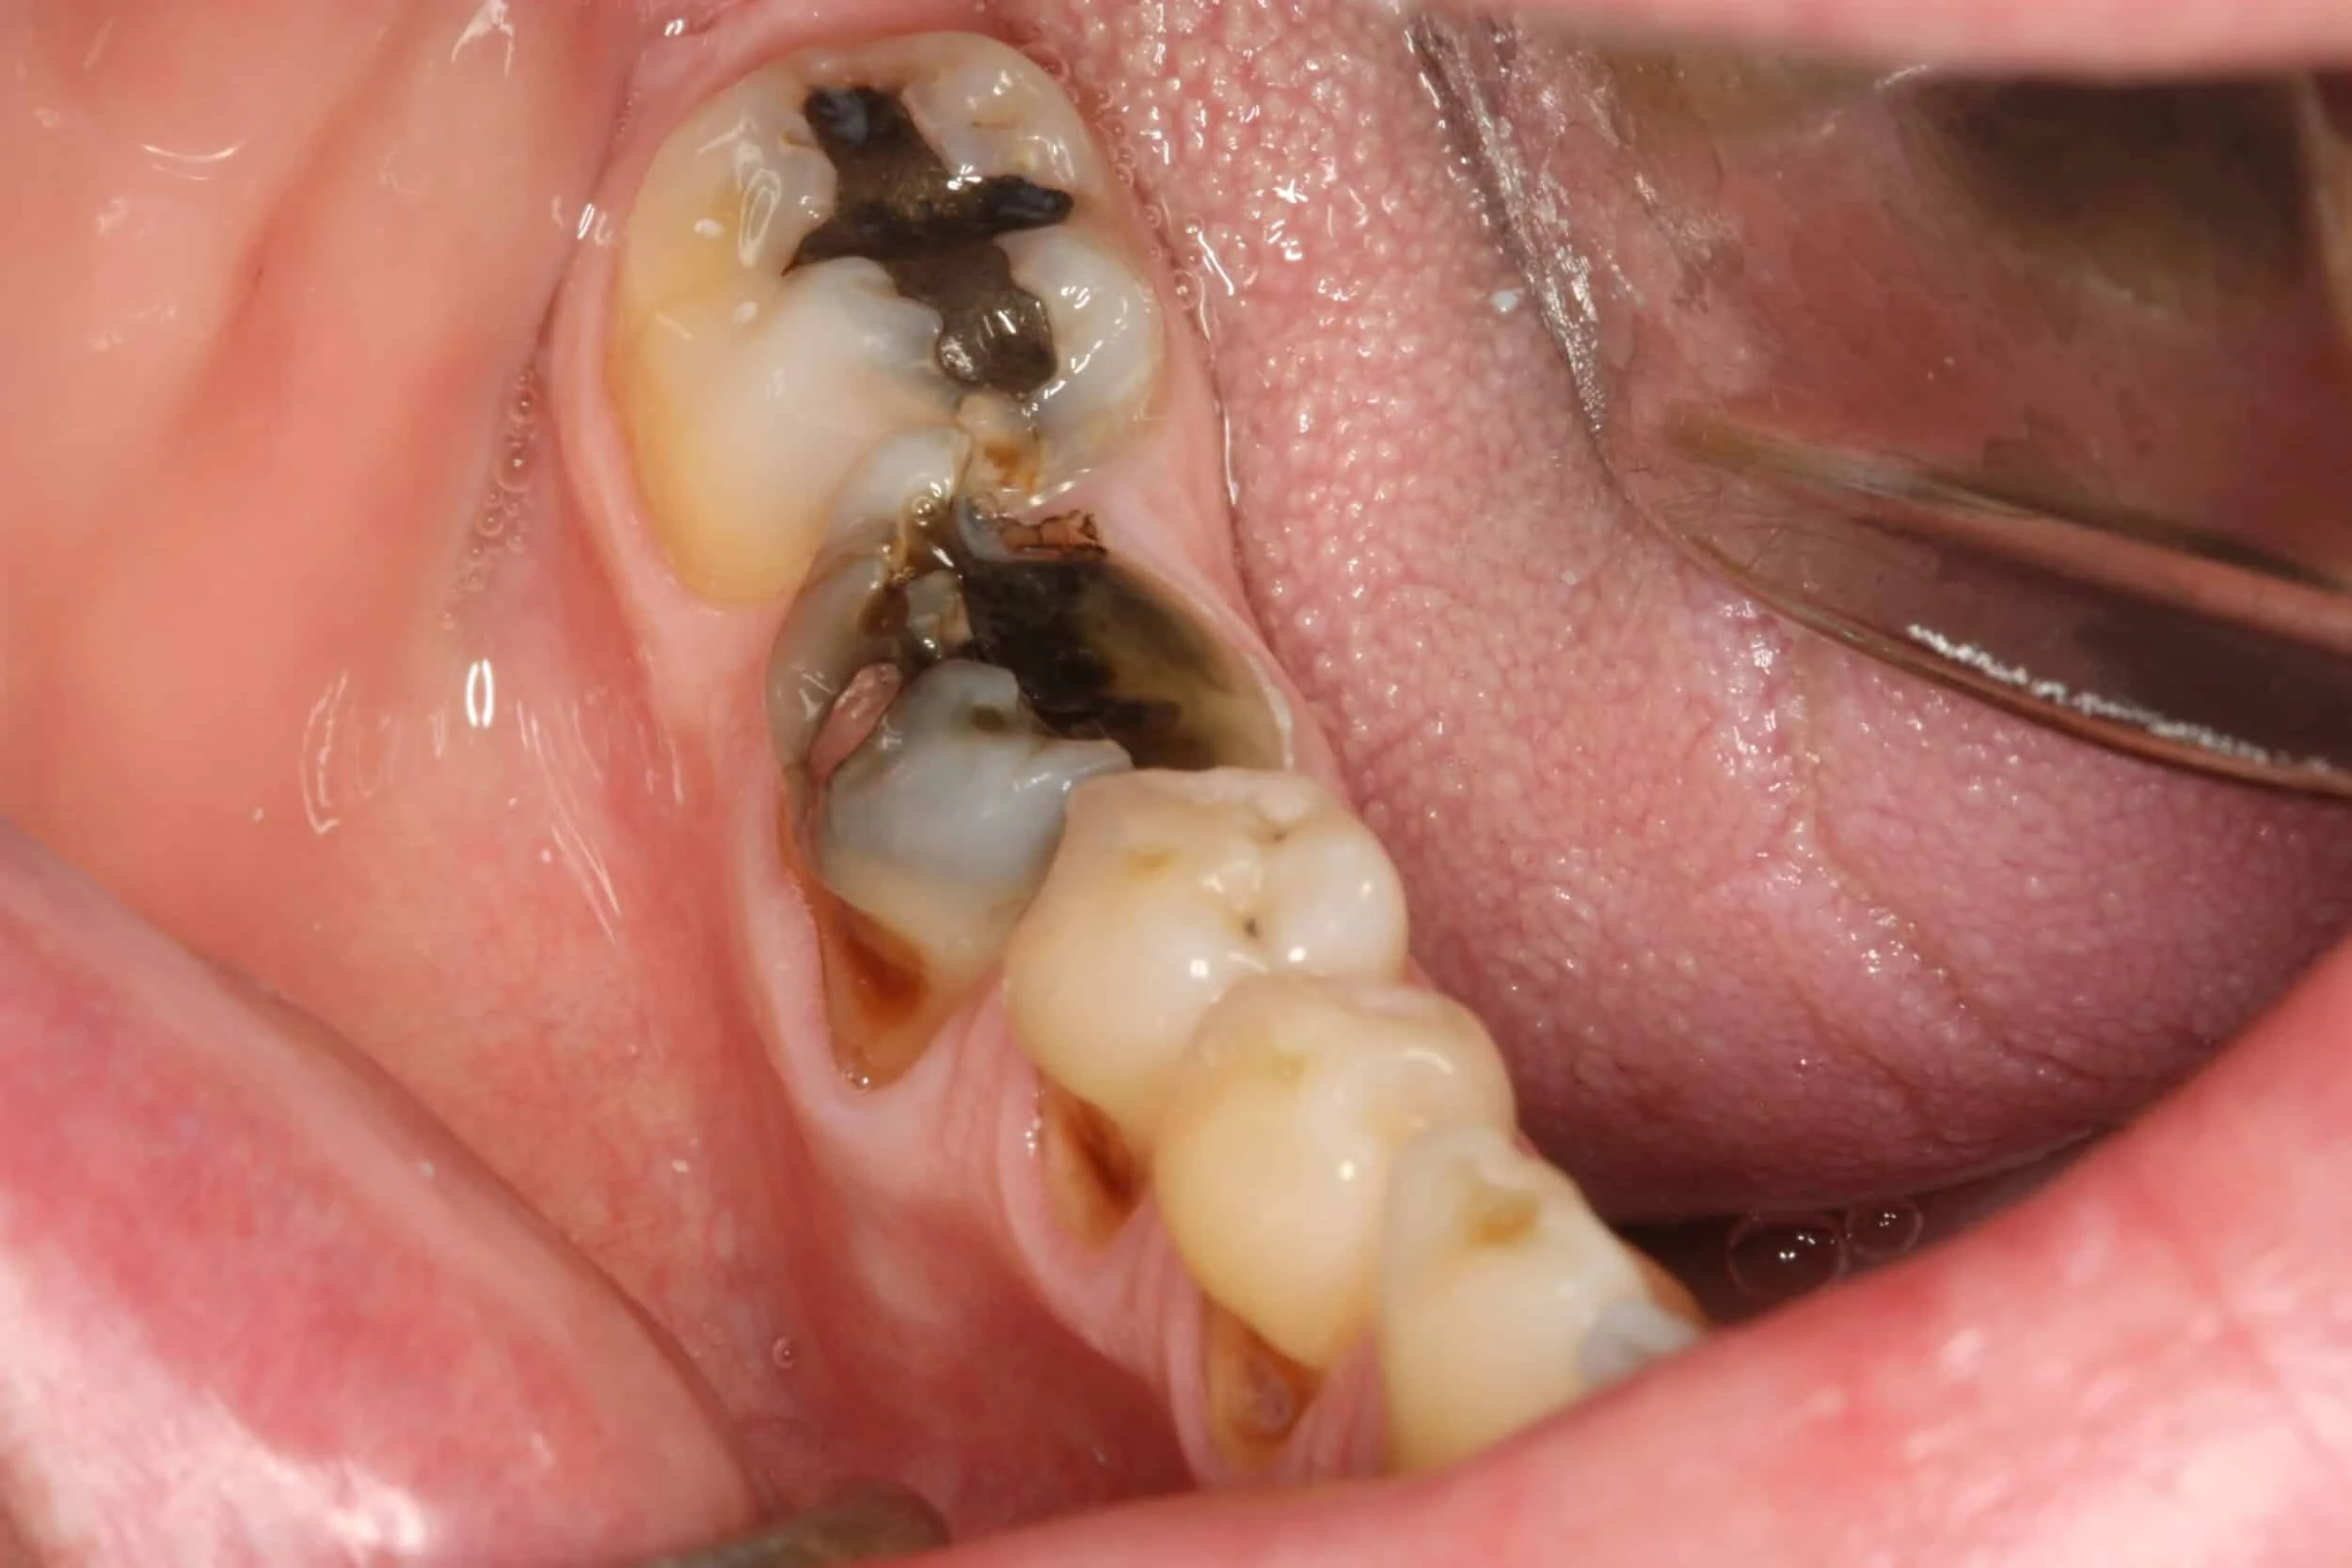

- Carie Profonda:

- Se la carie ha raggiunto la polpa del dente e l’infezione non può essere trattata con una terapia canalare.